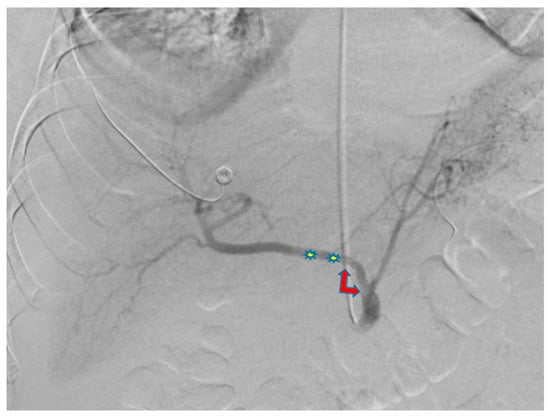

Use of Transradial Access to Install Two Sequential Stents for Pseudoaneurysms along the Celiac Artery and Common Hepatic Artery Axes